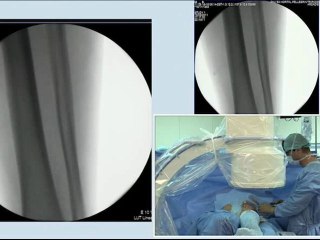

15 combined disease coronary artery stenting and left carotid artery stenting incathlab.com

Duration: 02:26